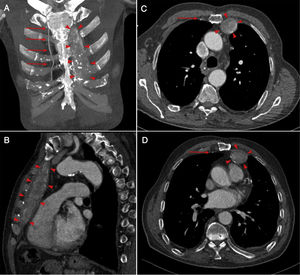

A 87-year-old man presented for evaluation of dyspnea and chest pain. There was no history of using any medication, previous surgery, and trauma. Laboratory tests performed for vasculitis and connective tissue disease are within normal limits. A mass was found in thoracic CT adjacent to the thoracic wall corresponding to a thrombosed left internal mammary artery aneurysm (Figure 1). He had not any type of abnormality such as aberrant right subclavian artery. Surgical treatment was not performed due to the age of the patient.

Internal mammary artery aneurysm is a rare but life-threatening condition. It is generally intragenic or traumatic, but can also be related to vasculitis or connective disease such as Marfan and Ehlers-Danlos. These aneurisms are very rarely idiopathic. Surgical and endovascular methods are generally used in treatment.1,2 Giant internal mammary artery aneurisms can present as a mass dependent from the chest wall.